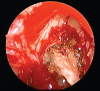

Background: Chronic rhinosinusitis (CRS) is one of the most common chronic medical conditions, with a significant impact on patient quality of life. CRS is broadly classified into two groups: CRS with nasal polyposis (CRSwNP) and CRS without NP (CRSsNP). Clinically, the major subtypes of CRSwNP may be divided into eosinophilic chronic rhinosinusitis (e.g., allergic fungal rhinosinusitis and aspirin-exacerbated respiratory disease [AERD]) and nasal polyps associated with neutrophilic inflammation (e.g., cystic fibrosis [CF]). CF is characterized by mutation of the gene encoding the CF transmembrane conductance regulator. Functional endoscopic sinus surgery is usually required for most NP patients with increased frequency in patients with AERD. This study provides a review of the epidemiology and major classification of CRSwNP.